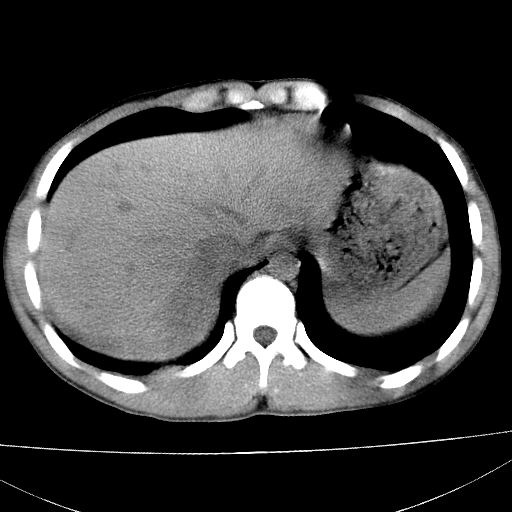

标题: CT15860:男,21岁,腹部外伤2小时伴胸疼。 [打印本页]

标题: CT15860:男,21岁,腹部外伤2小时伴胸疼。

肝脏及肾脏明显有损伤性改变并激发腹腔内积液(血),以肝脏撕裂及肾周积血显著。

1)肝破裂伴腹腔积液(血)。2)右肾破裂伴右肾包膜下及肾周血肿。3)腹部空腔脏器穿孔可能。4)右侧少量胸腔积液(血)。

肝右叶及右肾均见挫伤破裂出血。